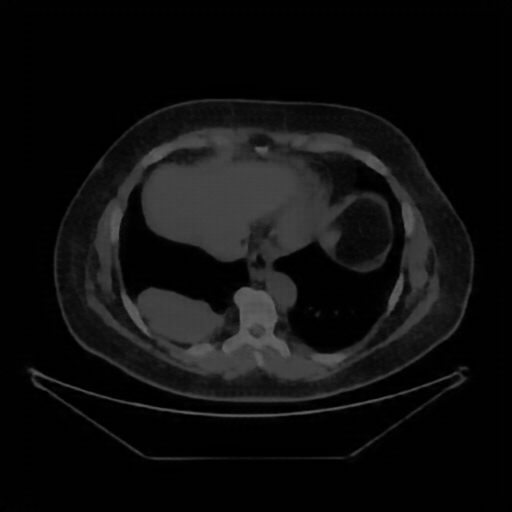

Generated VENOUS CT scan (A→B translation)

No window - Raw intensity values

Generated VENOUS CT scan (A→B translation)

Lung window (WL -600, WW 1500 → Low −1350, High +150)

Generated VENOUS CT scan (A→B translation)

Mediastinum window (WL 40, WW 400 → Low −160, High +240)

Image Grid

4×3 grid: Rows show different image types (Original NATIVE, Reconstructed NATIVE, Original VENOUS, Generated VENOUS), Columns show windowing techniques (No Window, Lung Window, Mediastinum Window)

Native→Venous Translation Metrics (Generated Venous vs Real Venous)

Targeted Slice 70 - Network-Normalized Analysis (Generated vs Real Venous)

0.263

SSIM Score

0.717

RMSE

0.667

MAE